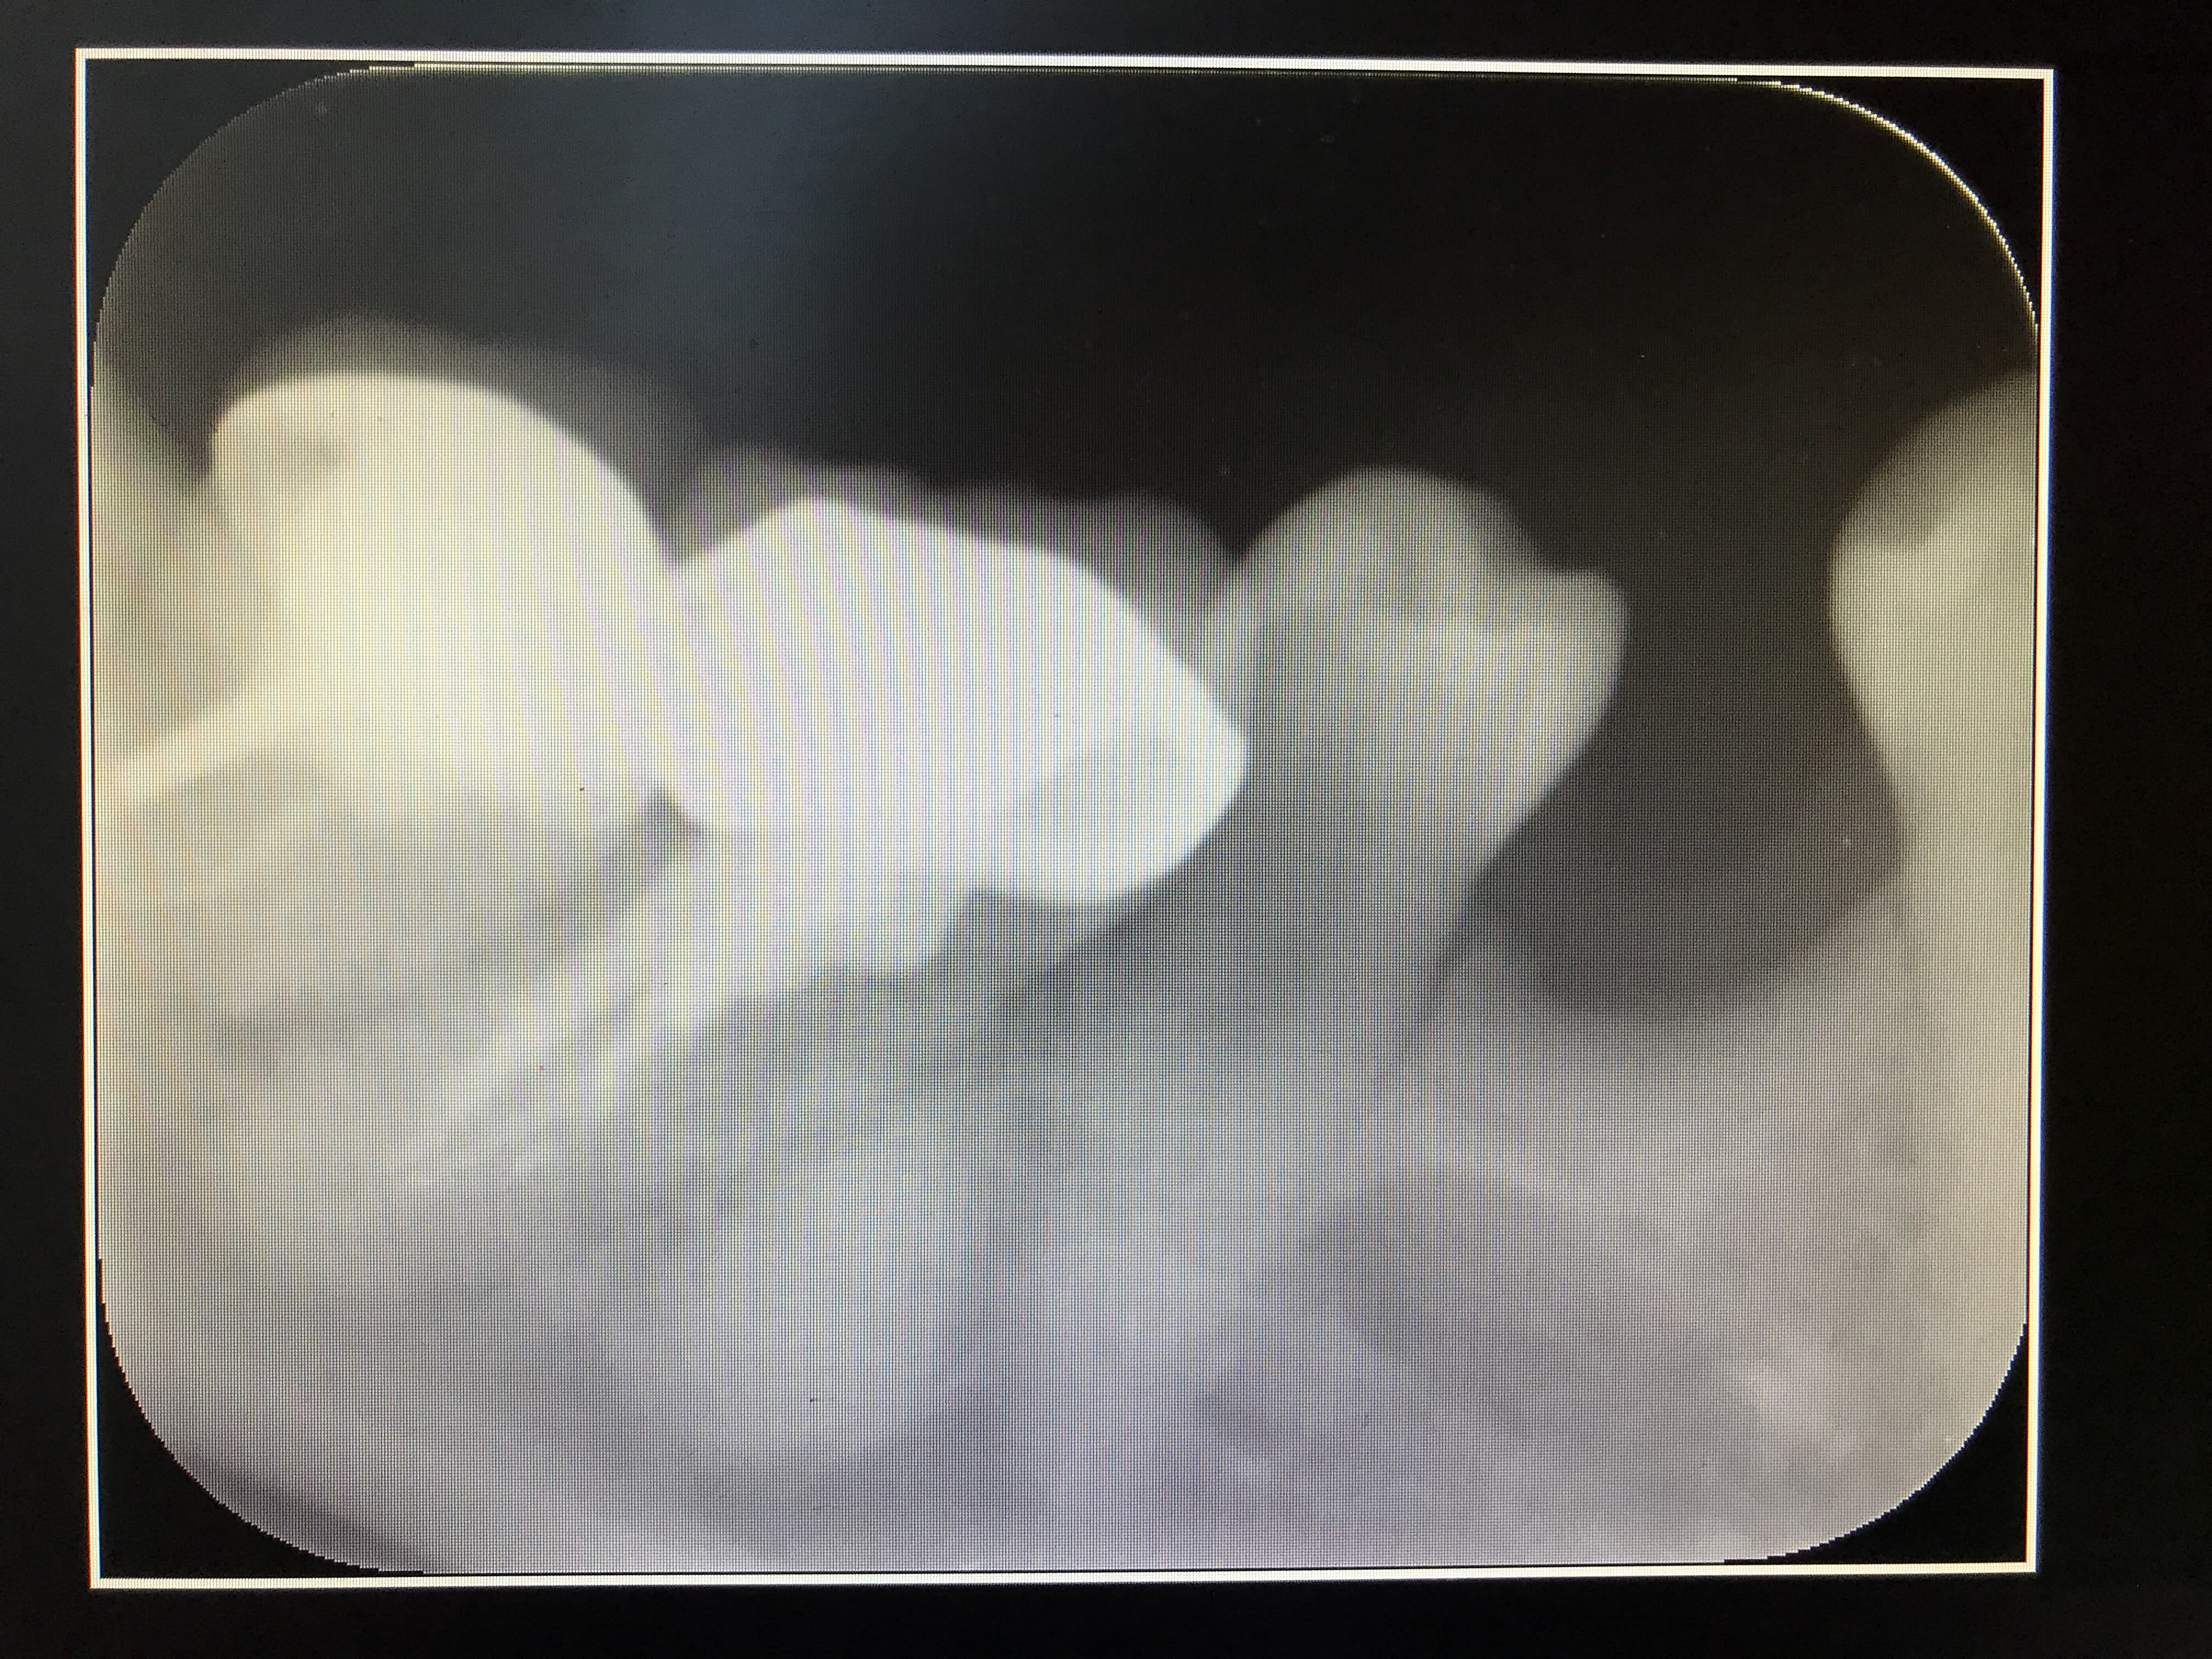

À votre avis qu'est ce que c’est ?

Y a une subtilité :)

je mets un jeton sur lithiase du coup, pourtant ça semble bien dans le nonos

Hey ben figure toi que non , le mec a fait une séparation de racine , a laissé la racine M qui a été recouverte au dessus par l’os et il a foutu une couronne par dessus la racine D :))